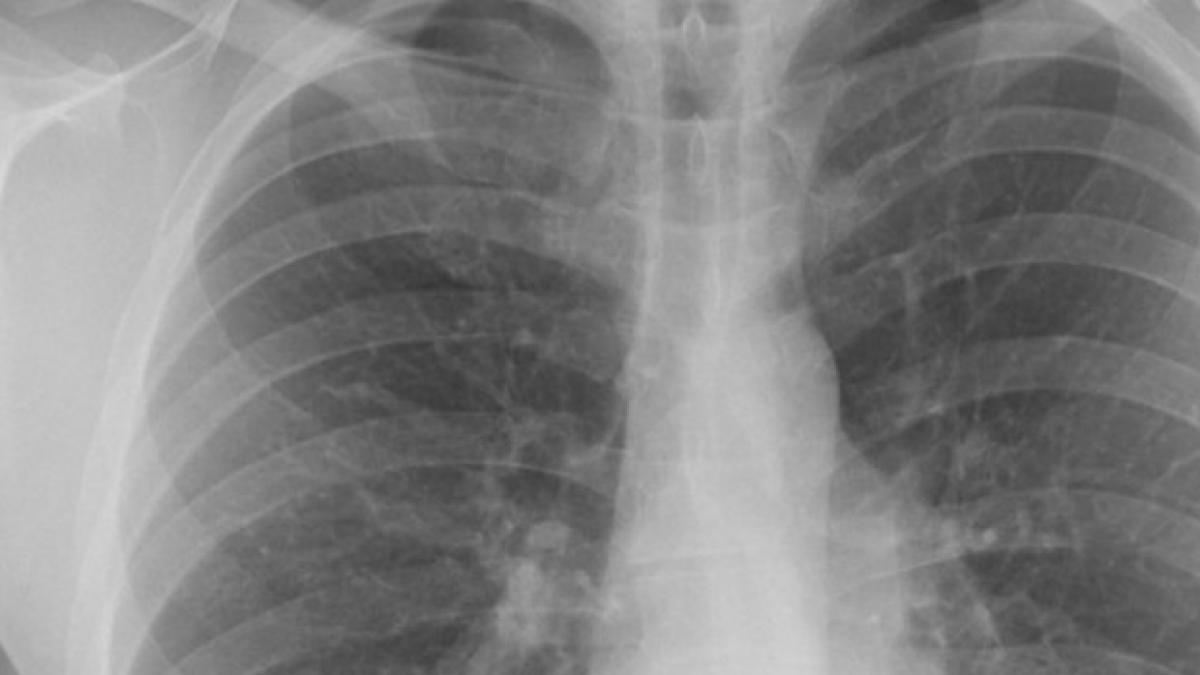

O femeie, în vârstă de 66 de ani din Massachusetts, Statele Unite, şi-a fracturat o coastă după un acces de tuse.

Pe partea intercostală dreaptă s-a observat vânătaia care indica un traumatism sever, iar analizele tomografice au arătat că a noua coastă era fracturată, scrie Live Science.

Femeia avea tuse convulsivă, care este o boală respiratorie cauzată de bacteria numită Bordetella pertussis.